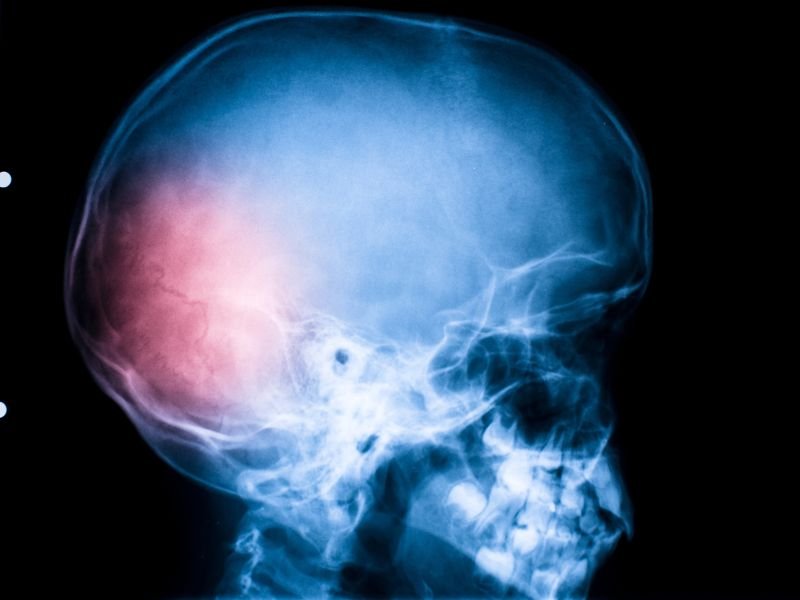

O traumatismo craniano é uma lesão que afeta o crânio e, muitas vezes, o cérebro. Ele ocorre quando um impacto súbito ou uma força externa causa dano à cabeça, podendo levar a uma variedade de consequências, desde leves, como concussões, até graves, como hemorragias intracranianas. Essa condição pode resultar em complicações temporárias ou permanentes, dependendo da gravidade do trauma.

Diagnóstico de Traumatismos Cranianos

O diagnóstico de um traumatismo craniano geralmente envolve uma combinação de exames físicos e de imagem. O médico pode realizar uma tomografia computadorizada (TC) ou uma ressonância magnética (RM) para avaliar a extensão da lesão e identificar possíveis danos cerebrais.